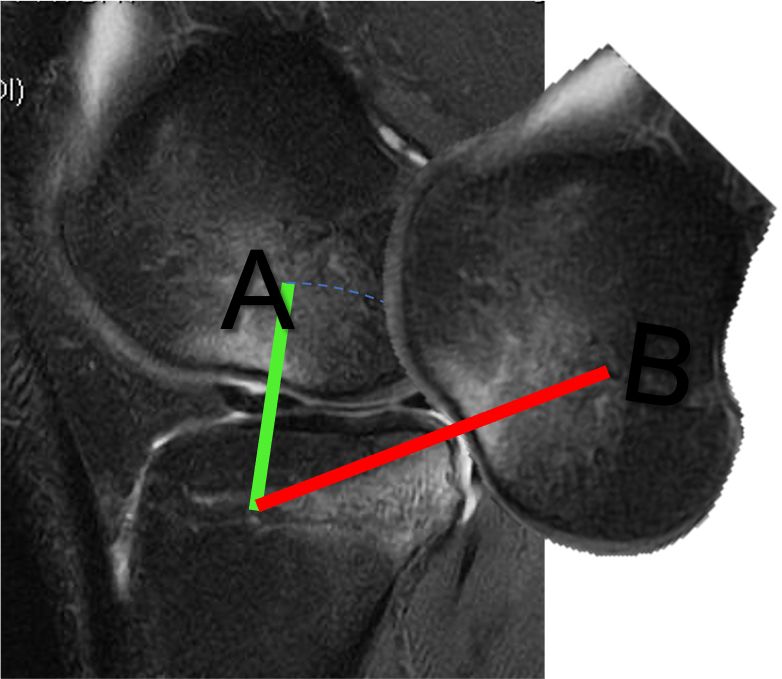

Intra-articular injuries mainly include medial or lateral meniscal injuries. More specific lesions, such as those of the medial meniscal ramp and the meniscal roots, in particular of the external meniscus, are also experienced (29,30) (Figure 7). Cartilage injuries should also not be overlooked because they are important for the long-term outcome of the knee. The prevalence of medial meniscal ramp injuries is estimated at 15.5–24% (29,31,32).

Meniscal root injuries also play a role in the rotational instability of the knee, in particular external meniscal root injuries (35,36). The prevalence of external meniscus root injuries ranges from 6.6%– 13.5% (30,37). These injuries should be diagnosed and treated simultaneously (Figure 8).